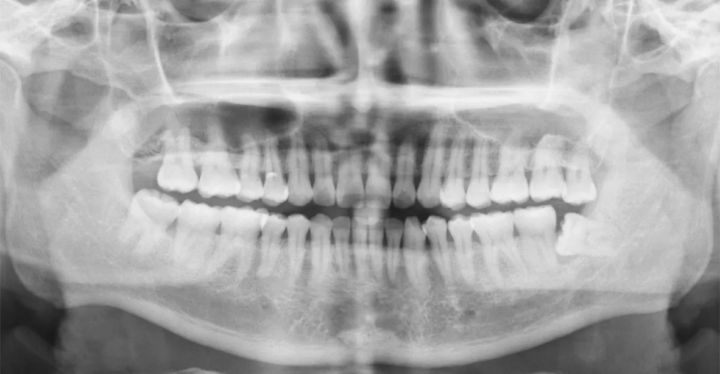

¿𝗤𝘂𝗶é𝗻 𝗺𝗮𝗻𝗱𝗮 𝗿𝗲𝗮𝗹𝗺𝗲𝗻𝘁𝗲 𝗲𝗻 𝘁𝘂 𝘁𝗿𝗮𝘁𝗮𝗺𝗶𝗲𝗻𝘁𝗼? 👑🦷 Soy la @Dra. Marta Cuadra y hoy quiero que identifiques al "culpable" de que tus casos se alarguen. En la biomecánica de alineadores, existe lo que yo llamo el Diente Director (o Movimiento Guía). Es ese diente que consume el mayor número de etapas y marca el ritmo de todo el ClinCheck. Si no identificas este diente desde el inicio, estarás forzando movimientos sin haber creado el espacio necesario. Es como intentar aparcar un coche donde no hay sitio. Entender la secuencia y la predictibilidad es lo que me ha permitido ser ortodoncista experta en España. Si dominas al Diente Director, dominas el tiempo de tu consulta. Hablemos de tus casos: ¿𝗤𝘂é 𝗱𝗶𝗲𝗻𝘁𝗲 𝘀𝘂𝗲𝗹𝗲 𝘀𝗲𝗿 𝘁𝘂 "𝗽𝗲𝗱𝗿𝗮 𝗲𝗻 𝗲𝗹 𝘇𝗮𝗽𝗮𝘁𝗼": 𝗲𝗹 𝟭𝟮 𝗼 𝗲𝗹 𝗰𝗮𝗻𝗶𝗻𝗼 𝗶𝗻𝗳𝗲𝗿𝗶𝗼𝗿? ¿𝗥𝗲𝗱𝘂𝗰𝗲𝘀 𝗹𝗮 𝘃𝗲𝗹𝗼𝗰𝗶𝗱𝗮𝗱 𝗱𝗲 𝗰𝗼𝗿𝗿𝗲𝗰𝗰𝗶ó𝗻 𝗲𝗻 𝗹𝗼𝘀 𝗱𝗶𝗲𝗻𝘁𝗲𝘀 𝗾𝘂𝗲 𝘁𝗶𝗲𝗻𝗲𝗻 𝗺𝘂𝗰𝗵𝗮 𝗿𝗼𝘁𝗮𝗰𝗶ó𝗻? ¿𝗨𝘀𝗮𝘀 𝗮𝘂𝘅𝗶𝗹𝗶𝗮𝗿𝗲𝘀 𝗼 𝗽𝗿𝗲𝗳𝗶𝗲𝗿𝗲𝘀 𝘀𝗲𝗰𝘂𝗲𝗻𝗰𝗶𝗮𝗿 𝗲𝗹 𝗺𝗼𝘃𝗶𝗺𝗶𝗲𝗻𝘁𝗼 𝗲𝗻 𝗲𝗹 𝘀𝗼𝗳𝘁𝘄𝗮𝗿𝗲?

¿𝗦𝗮𝗯í𝗮𝘀 𝗾𝘂𝗲 𝗲𝗹 𝟵𝟬% 𝗱𝗲 𝗹𝗼𝘀 𝗺𝗼𝗻𝘁𝗮𝗷𝗲𝘀 𝗱𝗶𝗴𝗶𝘁𝗮𝗹𝗲𝘀 𝗲𝘀𝘁á𝗻 𝗺𝗮𝗹 𝗼𝗿𝗶𝗲𝗻𝘁𝗮𝗱𝗼𝘀? 📐😲 Soy la @Dra. Marta Cuadra y hoy hablamos del plano oclusal. Si no ajustas la inclinación del maxilar en tu ClinCheck inicial, estarás programando un torque que no es real en la boca de tu paciente. Un error de 5 grados en el software se traduce en un desajuste total en la finalización. Yo siempre uso la herramienta de plano oclusal guiándome por la fotos de sonrisa. Como Invisalign Diamond Apex, sé que el éxito empieza en un montaje preciso. No es un fallo del sistema, es un fallo de planificación inicial. Hablemos de precisión: ¿𝗔𝗷𝘂𝘀𝘁𝗮𝘀 𝗹𝗮 𝗵𝗲𝗿𝗿𝗮𝗺𝗶𝗲𝗻𝘁𝗮 𝗱𝗲 "𝗣𝗹𝗮𝗻𝗼 𝗢𝗰𝗹𝘂𝘀𝗮𝗹" 𝗼 𝗱𝗲𝗷𝗮𝘀 𝗹𝗮 𝗾𝘂𝗲 𝘃𝗶𝗲𝗻𝗲 𝗽𝗼𝗿 𝗱𝗲𝗳𝗲𝗰𝘁𝗼? ¿𝗘𝘀𝗰𝗮𝗻𝗲𝗮𝘀 𝘀𝗲𝗻𝘁𝗮𝗱𝗼 𝗼 𝘁𝘂𝗺𝗯𝗮𝗱𝗼? (𝗥𝗲𝗰𝘂𝗲𝗿𝗱𝗮 𝗾𝘂𝗲 𝗹𝗮 𝗽𝗼𝘀𝗶𝗰𝗶ó𝗻 𝗰𝗮𝗺𝗯𝗶𝗮 𝗹𝗮 𝗼𝗰𝗹𝘂𝘀𝗶ó𝗻). ¿𝗖𝗼𝗺𝗽𝗮𝗿𝗮𝘀 𝗲𝗹 𝗺𝗼𝗻𝘁𝗮𝗷𝗲 𝘃𝗶𝗿𝘁𝘂𝗮𝗹 𝗰𝗼𝗻 𝗹𝗮𝘀 𝗳𝗼𝘁𝗼𝘀 𝗳𝗮𝗰𝗶𝗮𝗹𝗲𝘀 𝗱𝗲𝗹 𝗽𝗮𝗰𝗶𝗲𝗻𝘁𝗲?

𝗨𝗻𝗮 𝗹í𝗻𝗲𝗮 𝗺𝗲𝗱𝗶𝗮 𝗱𝗲𝘀𝘃𝗶𝗮𝗱𝗮 𝗲𝘀 𝘀𝗼𝗹𝗼 𝗹𝗮 𝗽𝘂𝗻𝘁𝗮 𝗱𝗲𝗹 𝗶𝗰𝗲𝗯𝗲𝗿𝗴. 🧊🚩 Soy la @Dra. Marta Cuadra y antes de intentar moverla como una "cortina" en el ClinCheck, debemos saber por qué está ahí. ¿Es una desviación dentaria, esquelética o funcional por una interferencia? Como arquitecta de sonrisas, sé que mover las líneas medias sin diagnosticar el lado de masticación es un error. Si la mandíbula se desplaza funcionalmente, hay que quitar el "tope" antes de alinear. En mi planificación, proinclino, hago IPR asimétrico y retroinclino hacia el lado correcto. Es pura estrategia de espacios. Dime una cosa: 1. ¿𝗖ó𝗺𝗼 𝘀𝗮𝗯𝗲𝘀 𝘀𝗶 𝘁𝘂 𝗱𝗲𝘀𝘃𝗶𝗮𝗰𝗶ó𝗻 𝗲𝘀 𝗳𝘂𝗻𝗰𝗶𝗼𝗻𝗮𝗹 𝗼 𝗲𝘀𝘁𝗿𝘂𝗰𝘁𝘂𝗿𝗮𝗹 𝗲𝗻 𝗹𝗮 𝗽𝗿𝗶𝗺𝗲𝗿𝗮 𝘃𝗶𝘀𝗶𝘁𝗮? 2. ¿𝗨𝘀𝗮𝘀 𝗲𝗹á𝘀𝘁𝗶𝗰𝗼𝘀 𝗮𝘀𝗶𝗺é𝘁𝗿𝗶𝗰𝗼𝘀 𝗱𝗲𝘀𝗱𝗲 𝗲𝗹 𝗮𝗹𝗶𝗻𝗲𝗮𝗱𝗼𝗿 𝟭 𝗽𝗮𝗿𝗮 𝗰𝗼𝗿𝗿𝗲𝗴𝗶𝗿 𝗹í𝗻𝗲𝗮𝘀 𝗺𝗲𝗱𝗶𝗮𝘀? 3. ¿𝗾𝘂é 𝗵𝗮𝗰𝗲𝘀 𝘀𝗶 𝗹𝗮 𝗹í𝗻𝗲𝗮 𝗺𝗲𝗱𝗶𝗮 𝘀𝘂𝗽𝗲𝗿𝗶𝗼𝗿 𝗻𝗼 𝗰𝗼𝗶𝗻𝗰𝗶𝗱𝗲 𝗰𝗼𝗻 𝗲𝗹 𝗳𝗿𝗲𝗻𝗶𝗹𝗹𝗼 𝗹𝗮𝗯𝗶𝗮𝗹? #LineaMedia #DiagnosticoDental #DraMartaCuadra #OrtodonciaFuncional #ClinCheckTips